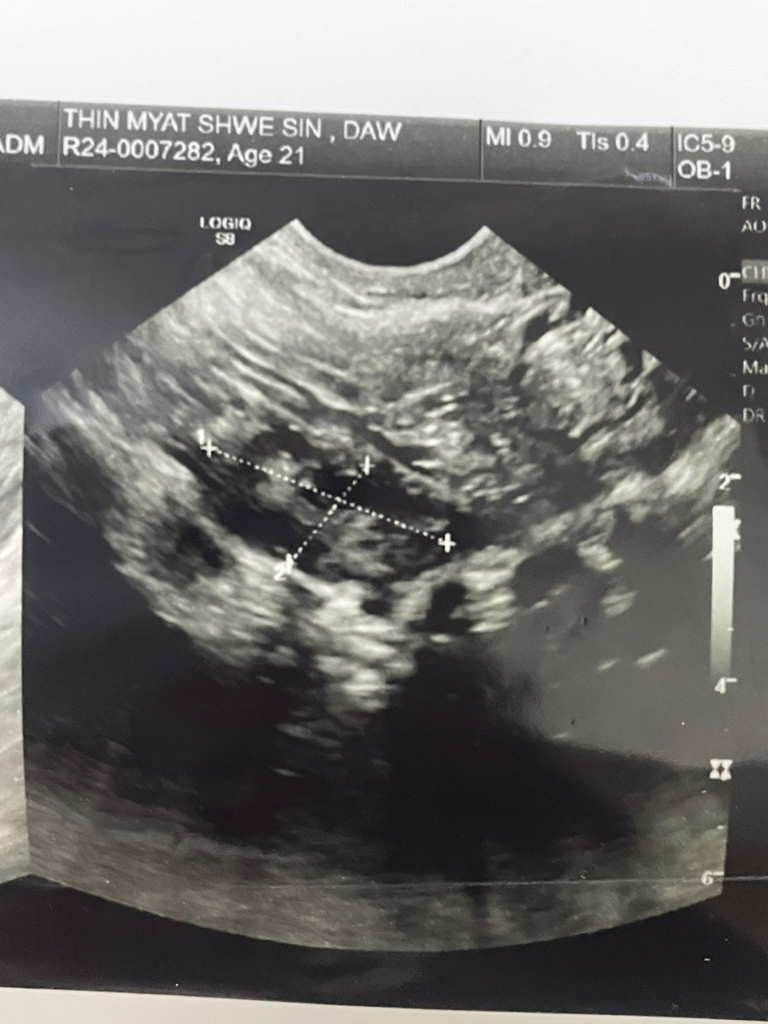

2023년12월25일 마지막으로 관계 후 계속 관계가 없었는데 2024년2월16일에 임신했다고 합니다 병원에서는 4~5주차라고 합니다 (마지막 생리는 1월26일입니다)

초음파도 같이 첨부합니다

1.4~5주차라도 제가 아빠가 될 확률이 있나요?

2.병원에서 4~5주차라 이야기했는데 8~9주차랑 헷갈릴 수있나요?

3.병원에서는 아직 아기집이 작고 쌍둥이라고 3주후에 다시 검사하자고하는데 아기집 작고 쌍둥이라서 위협할 수 있나요?3주동안 아기를 지킬수있는 방법좀 알려주세요

임신은 수정란이 자궁에 착상한 때부터 시작됩니다. 수정란이 자궁에 착상하는 데는 보통 6~7일이 걸리므로, 마지막 관계 후 1달이면 임신할 수 있습니다. 따라서 2023년 12월 25일 마지막으로 관계한 후 2024년 2월 16일에 임신했다고 하면, 수정란은 2024년 2월 10일경에 자궁에 착상한 것으로 추정할 수 있습니다. 따라서 4~5주차라고 하는 병원의 진단은 맞습니다. 임신 초기에는 아기집이 작고 쌍둥이일 가능성이 높습니다. 쌍둥이는 한 번에 두 개의 수정란이 자궁에 착상하는 것으로, 아기집이 작고 쌍둥이일 가능성이 높습니다. 쌍둥이는 임신 중 합병증이 발생할 위험이 높으므로, 병원에서 정기적으로 검사를 받아야 합니다. 아기집이 작고 쌍둥이일 가능성이 높다고 해서 아기를 지킬 수 있는 방법은 없습니다. 다만, 임신 초기에는 쉬고 충분한 휴식을 취하는 것이 좋습니다. 또한, 균형 잡힌 식사를 하고 과도한 스트레스를 받지 않는 것이 좋습니다.